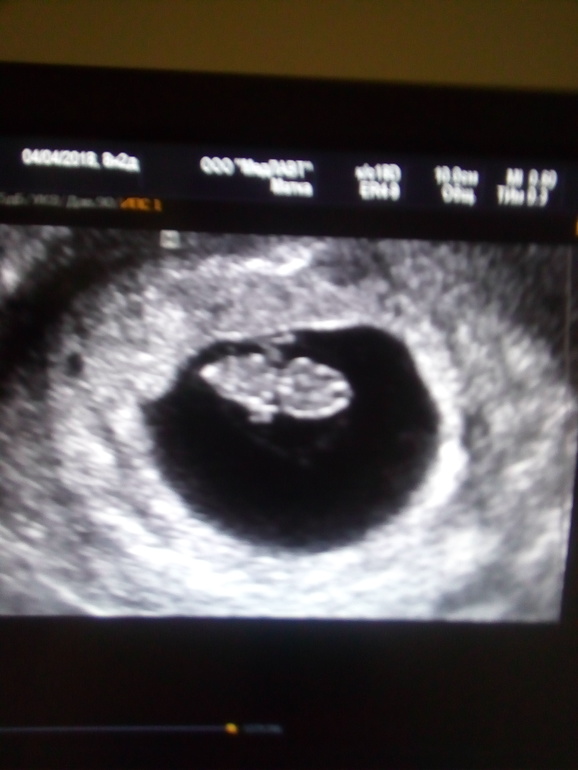

Сегодня я увиделась со своим малышом! Это непередаваемые ощущения! Самый лучший малыш в мире 😍😊! По УЗИ всё соответствует срокам и сб - 162уд.А теперь история: 1. Второго ребеночка мы захотели 4 года назад. Так как первый получлся с первой попытки и беременность протекала легко и без осложнений, то я думала, что и вторая сложится также. 2. Как и планировала забеременела сразу и была уверена, что у меня всё хорошо. Но вдруг заболела сильно с температурой высокой и рвотой. Когда выздоровела решила перед учетом пойти на УЗИ. И тут услышала приговор - анэмбриония и миома матки 6см! То, что это был шок - ничего не сказать! Потом переделывала еще раза три наверно, но срок уже был больше 9 недель и надежды на чудо улетучились! Врачи по УЗИ говорили мне, такое бывает, естественный отбор и т.д. типа, второй раз придешь будет всё окей " А когда я попала в больницу на чистку, меня взяла заведующая отделением, очень толковая храч, хирург с большой буквы! Сразу сказала, ты что! Такую миому надо удалять. Я ее спросила, это ведь не из-за миомы? А она, в том числе может быть и из-за нее! Я пережив весь этот ужас, и вернувшись к обычной жизни, решила всё поизучать про беременность с миомами. И начитавшись статей из интернета решила, что всё таки наверно не в миоме было дело, но беременнеть не спешила, всё же страх взял свое! 3. И тут на тебе! Где-то мес. через 7, я узнаю, что беременна! О боже! Я не была к этому готова, так как в опасные дни мы предохранялись! В этот раз всё протекала хорошо, самочувствие нормальное. Один раз правда было небольшое кровотечение- капля размером со сливу, один раз и всё прошло. Я начитавшись, что это возможно, не придала этому больше значения. И когда на УЗИ мне ставят диагноз ЗБ на сроке 5-6 недель я впадаю в отчаяние. Звоню этой же заведующей и рассказываю про ситуацию. Она конечно меня поругала, что так и без матки можно остаться. Миома выросла к тому моменту до 9 см! 4.После очередной чистки обсудили с ней мои дальнейшие действия и после подготовки к операции - удалять миому! О том как я настраивалась и боялась операции - отдельная тема 😂, но вообщем всё прошло хорошо и я быстро восстановилась. Мне разрешили беременность через пол года! Но я конечно, не была готова к этому так быстро, тем более мне рекомендовали перед планированием сделать МСГ труб, а я очень этого не хотела. 5. И вот спустя 1,5 года, подзабыв все страхи и переживания мы решили возобновить планирование! И вот проходят месяц, два, три... и всё тихо! Я начитавшись, что после операций часто бывает не проходимость труб, начинаю готовить себя к худшему... или нет, я отдаюсь на волю Божию! Думаю, если не дано мне второго ребеночка, то и нечего жизнь по больничкам тратить. 5. Но начитавшись и наслушавшись кучу историй поняла, что ни разу не проверяли мужа! Он идет сдавать спермограмму и та-дам! У нас астенозооспермия! Это был очередной шок для нас! Начали лечение и в апреле пересдаем результаты - а там на тебе - астено-тератозооспермия! Я вся в слезах и соплях почему так, ведь его ничего не беспокоит, не пьет, занимается спортом? Решили найти грамотного андролога и не сдаваться. Но его пришлось отложить, так так в этом же месяце месячные так и не пришли. Для нас это было чудо! И вот мои выводы, девочки: 1. Из-за миомы могут быть ЗБ, так как она забирает кровоток себе и малыш попросту задыхается! 2. После единичный миомы необязательно садиться на гормональные и входить в ИК. 3. После операции необязательно продувать трубы, если они были хорошие до! 4. Астено-тератозооспермия не приговор и не повод для ЭКО! 5. Всё получается, если довериться природе! В жизни всё так надо! Удачи, всем счастья, добра! 😍 P. S. Прикрепляю первое фото моего малыша!Милана